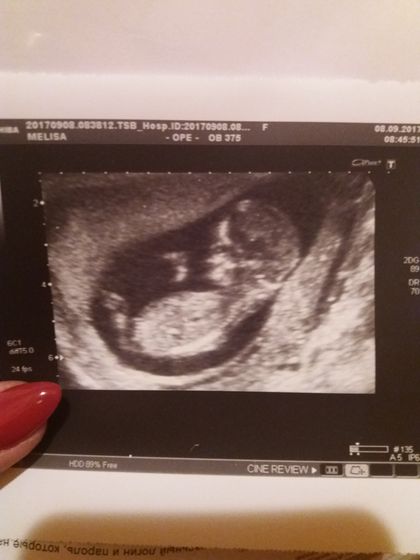

Вот и мы прошли первый скрининг) Как же я ждала этого дня! Столько волнения и радости) Увидела наконец наше маленькое чудо ? Узист сказал что у нас всё отлично! От счастья хочется кричать!!))))

Осталось дождаться результатов крови, надеюсь и там всё будет хорошо! ✊?